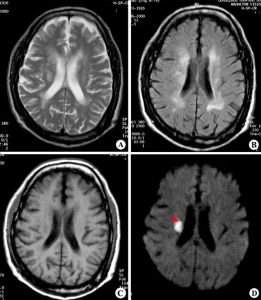

放射冠區腦梗塞產科

放射冠3、放射冠是指由內囊到大腦皮層間的放射狀纖維白質不同功能的各種投射纖維在其間的空間排列規律目前尚不完全清楚.由於放射冠纖維排列較分散此處的梗死常表現為局限的神經系統症狀